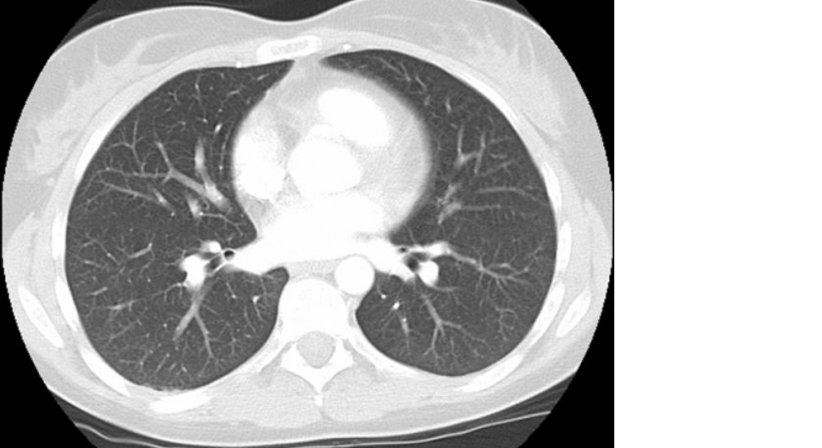

Die CT ist eine ausgezeichnete Methode zur Untersuchung und überlagerungsfreien Darstellung von Veränderungen im Körper.

Sie ist besonders zur Untersuchung der Lunge und des Bauchraumes geeignet.

Der Patient liegt hier auf einer bequemen Liege und wird durch eine große Öffnung von ca. 70 cm Durchmesser geschoben. In dieser Öffnung werden von verschiedenen Seiten Röntgenstrahlen durch den Körper geschickt und auf der gegenüberliegenden Seite des Rings registriert.

Durch die jeweiligen Abschwächungen der Strahlenenergie können mittels Computer Schnittbilder der untersuchten Region errechnet werden. Durch die Gabe von Kontrastmittel über die Vene kann die Aussagekraft der Untersuchung noch gesteigert werden. Kontrastmittel sind meist jodhältige Substanzen die sich in den verschiedenen Organen wie Leber, Nieren, Milz etc. anreichern. Durch Störungen oder Änderungen der Kontrastaufnahme ergeben sich Bilder, die Rückschlüsse auf die Charakteristik von Veränderungen zulassen.